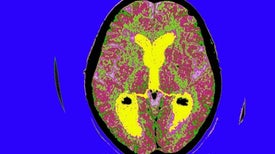

The main way the disease works is to disrupt communication between neurons, the specialized cells that process and transmit electrical and chemical signals between regions of the brain